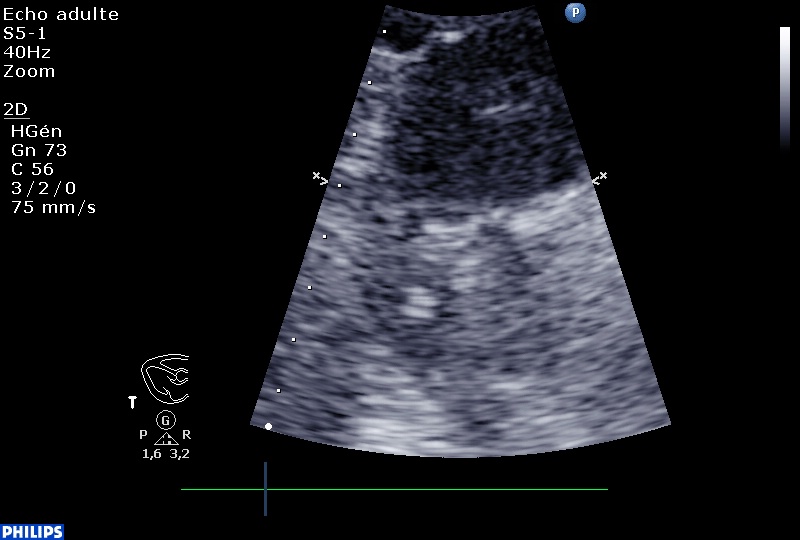

Sur cette coupe, on voit de haut en bas, la crosse de l’aorte au niveau de l’isthme et de l’artère sous clavière gauche, et en dessous, l’artère pulmonaire droite qui « plonge » en bas et à droite de l’écran.

En supra sternale, sous la crosse de l’aorte, on aperçoit un thrombus mobile dans l’artère pulmonaire doite :

Zoom sur le cadre précédent :

Il faut dire que, si l’on voit le petit bout du thrombus, c’est parce qu’il est ÉNORME!